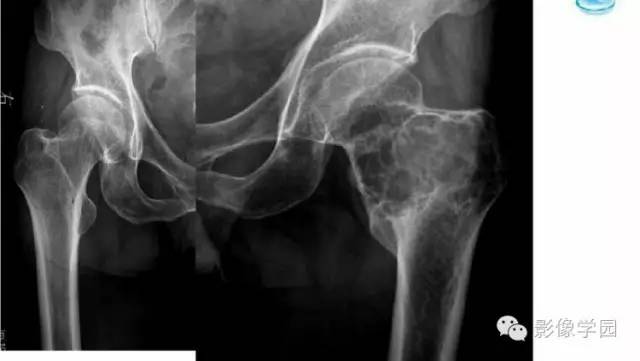

【病例】股骨软骨粘液样纤维瘤1例X线及MR影像表现